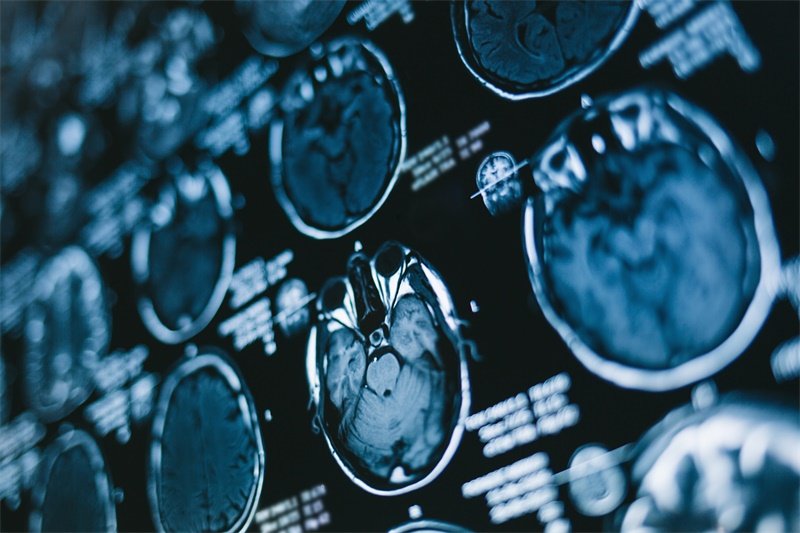

确诊前颅窝底实性占位通常需要经过多种检查手段的综合评估。常规的影像学检查如CT(计算机断层扫描)和MRI(磁共振成像)是基础而重要的诊断工具。CT能够快速显示出颅内结构的改变和病变的大小,MRI则能更清晰地显示肿瘤与周围脑组织的关系。